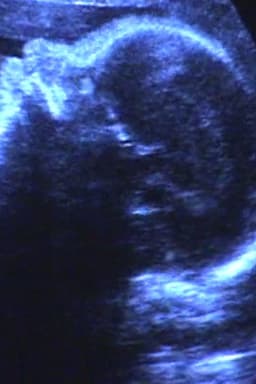

A Short Film for Lida — Now Showing